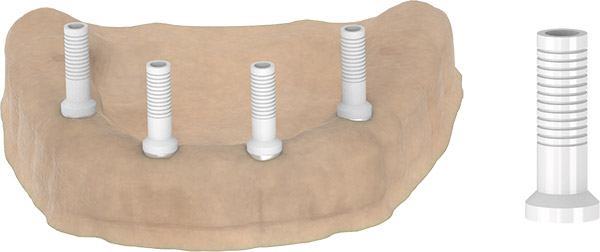

LABORATORY PROCESSES

- Mount the analogs carefully on impression pick up pieces.

- Prepare the impression for transfer.

- Cast high-quality material for the master model.

- The model is restored in the dental laboratory.

- Place the abutment on top.